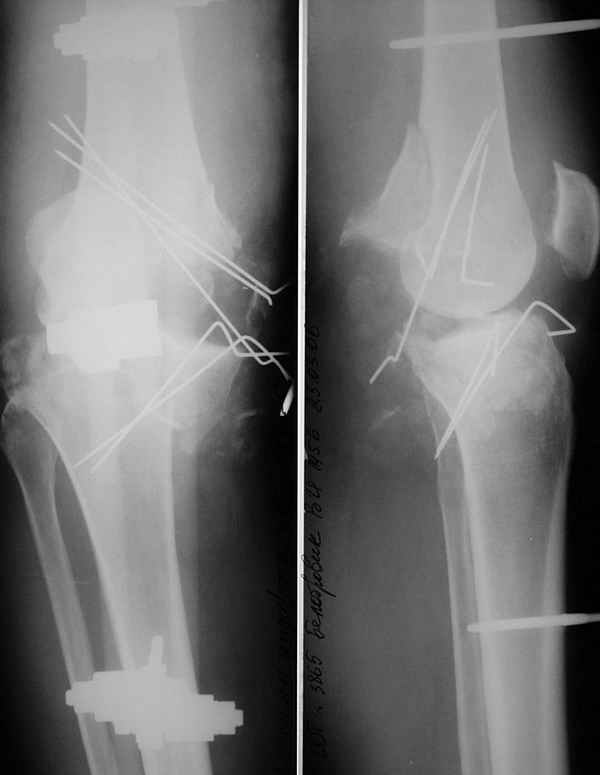

При поступлении - травматический шок 2 ст. При ревизии раны - отсутствие внутреннего мыщелка бедра, перелом внутреннего мыщелка б/б кости, нестабильность коленного сустава. Повреждений магистральных сосудов и нервов нет. Рваная лоскутная рана по внутренней поверхности колена.Выполнен адаптационный остесинтез остатков кости спицами и мостовидная трансартикулярная фиксация стержневым аппаратом внешней фиксации. Наводящие швы, частично - пластика по Хохутову.Сейчас раны заживают (местами с небольшими некрозиками, но в целом неплохо), встает вопрос о втором этапе лечения. Напрашивается вроде артродез коленного сустава.

>адаптационный остесинтез ... и мостовидная трансартикулярная фиксация

>стержневым аппаратом внешней фиксации.

1. Аппарат наружной фиксации наложен неплохо.

Прошу прощения за долгое молчание - ждал понедельника, чтобы сфотографировать современное состояние конечности. То, что было представлено на втором клиническом слайде - это 4-5 дней после операции (sorry за возможную путаницу). Итак свежее фото тут.